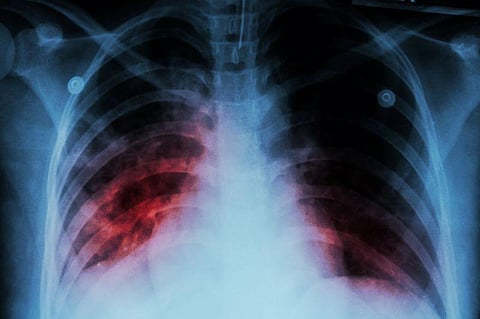

JUEVES, 23 de marzo de 2023 (HealthDay News) -- Los casos de tuberculosis (TB) aumentaron de nuevo en 2022, anunciaron el jueves las autoridades de salud de EE. UU.

Aun así, el aumento de un 5 por ciento, que equivalió a 8,300 casos, no alcanzó a los números más altos previos a la pandemia, según los Centros para el Control y la Prevención de Enfermedades (CDC) de EE. UU.

"El mensaje es claro y contundente: la TB sigue aquí. Por segundo año consecutivo, los casos de enfermedad por la TB han continuado en aumento en EE. UU., con unos incrementos preocupantes entre los niños pequeños y otros grupos con un mayor riesgo de enfermedad por la TB", comentó en un comunicado de prensa de los CDC el Dr. Philip LoBue, director de la División para la Eliminación de la Tuberculosis de la agencia.